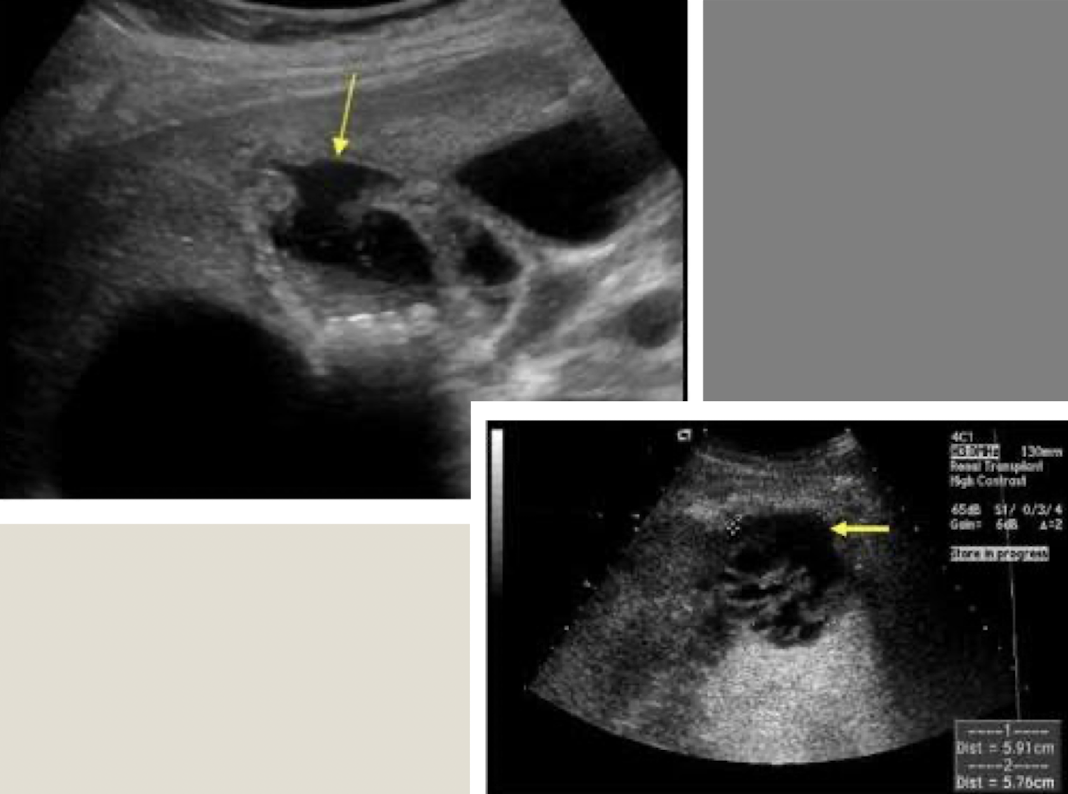

choledochal cysts

rare

congenital, focal, or diffuse dilation of biliary tree

MC in females with increased incidence in infants

Todani and colleagues classify into 5 types (depending on location)

Type 1 is MC

associated with gallstones, pancreatitis, or cirrhosis

SONO: choledochal cysts

cystic dilation of biliary tree

appear as true cysts in the RUQ

??

Type 5 choledochal cysts (Caroli’s disease)